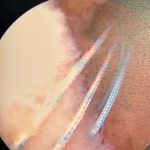

Surgical pictures

Anchor

Sutures

You can see from the bone spur outlined in red above that my tear was an caused by repetitive micro trauma over time. Eventually, the tendon became tattered and torn. All the years of weight training probably contributed to some of this, as well as my type 2 acromion. I ended up with three total anchors and a suture bridge repair.